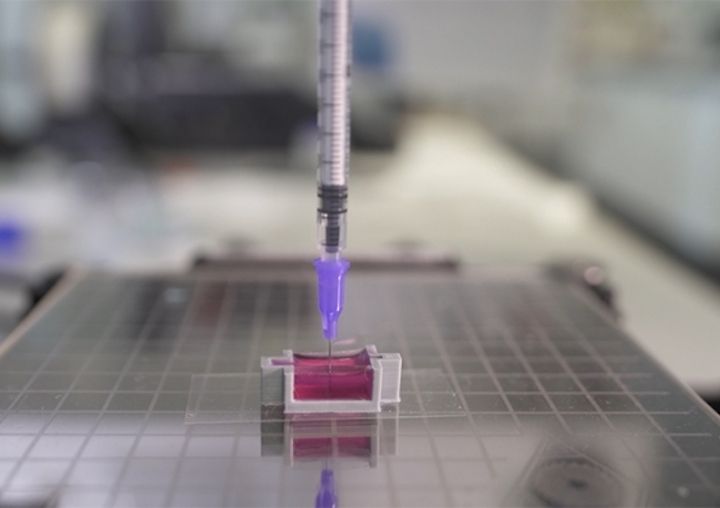

Researchers 3D Print Functional Blood Vessels Using Custom Bioink

Researchers have developed a method of 3D printing blood vessels, and that’s quite important.